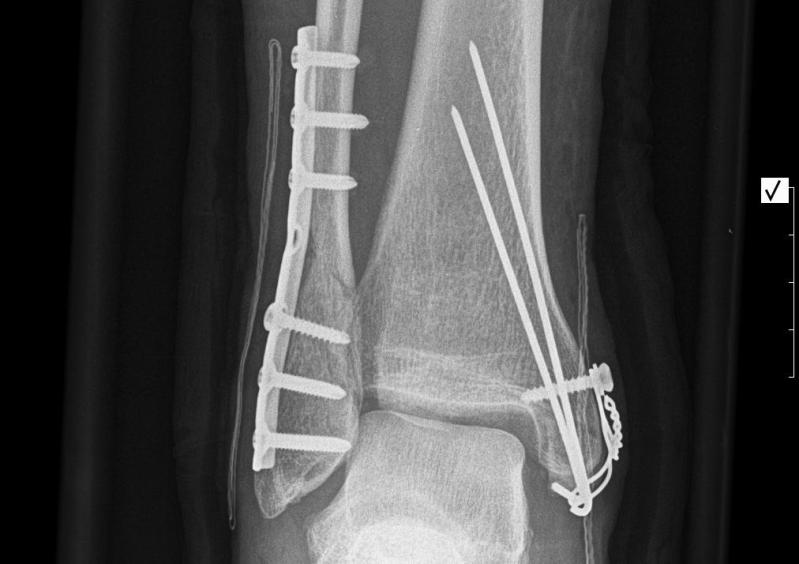

My ankle isn’t sore any more but it was, watch next…

Whooooooo Buddy!!! Owwwwwwww… did you do that unicycling?

Awesome pix.

I am glad that your recovery was strong.

Those pics make me shudder! :frowning:

Yes, he did that will unicycling.

AND it was during a shoot for national Dutch TV, so everybody saw it.

Thanks Peter,

I recovered (quickly)…

I managed to uni my first marathon in the year of recovery…

during the SM run… (a run of over 42 km crosscountry in the south of “mountyfull Netherlands”, hahah)

This year my first official one (Düsseldorf/ Germany) just 2 weeks after surgery ( dismounting the metal from my body) and just under 2 hours!!!